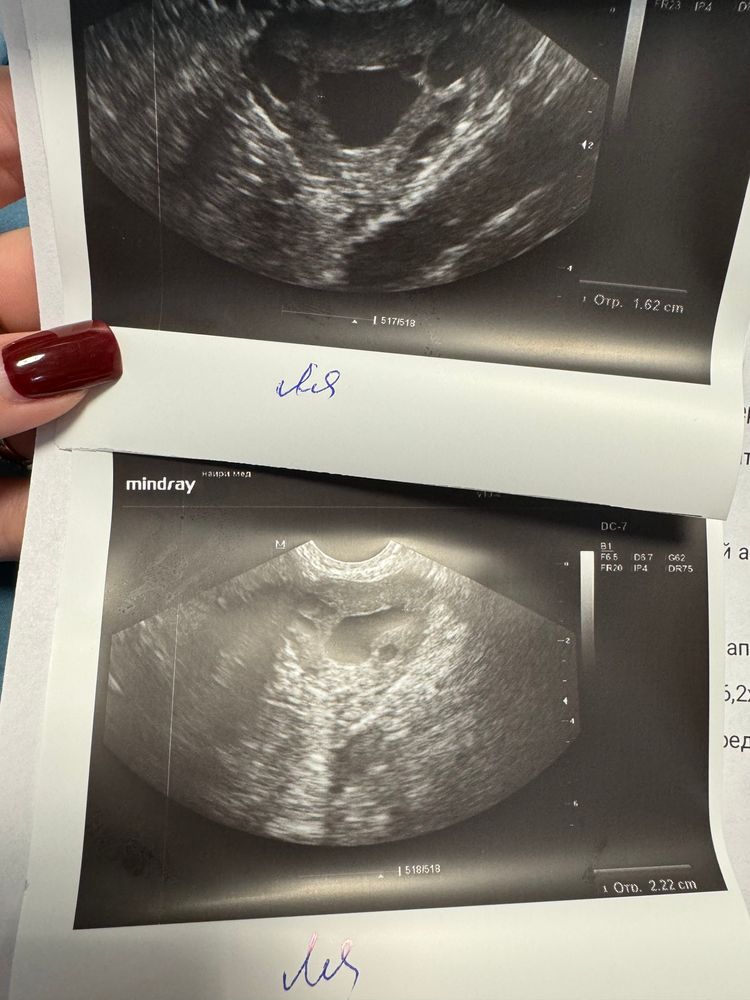

Так вот, забежала еще на УЗИ сегодня. А там: фолликул остался на месте 😱 Такое бывает вообще? 😐 В размерах не поменялся. А вот эндометрий на 7 день цикла уже 6,5 и трехслойный. (В том цикле был на 23 день цикла 5,5 однородный).

Это фолликулярная киста? Или что это, блин, такое? Могла ли я в том цикле заглушить овуляцию утрожестаном и фолликул поэтому остался? Миллион вопросов к организму, честно говоря 🙈